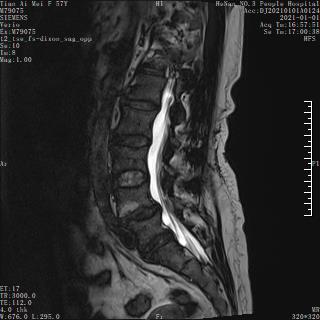

腰椎滑脱症

患者,女,57岁,2年前出现活动后腰部疼痛,保守治疗后稍缓解,1年前开始出现左臀部酸困不适,半个月前出现腰部及左髋部疼痛明显加重,伴左下肢麻木不适,为求进一步治疗来到我院椎间盘中心。

入院后,完善相关检查,诊断为腰椎滑脱症(L4/5),予以实施了全麻下UBE技术L4/5镜下融合滑脱复位内固定术。

术前MRI

术后MRI